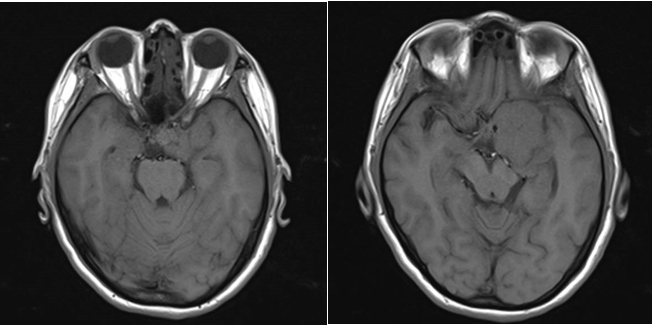

现病史:患者20天前无明显原因出现鼻酸,伴有异味感,继之出现全身不适,呈发作性,每次持续约1分钟左右,发作时意识清、精神可,对发病时情况记忆模糊,共发作3-4次,无意识模糊、复视。颅脑MRI平扫+强化示:鞍上池左侧可见不规则等T1等T2信号影,DWI呈等信号;明显均匀强化,与前床突、颈内动脉关系密切。

诊断:左侧蝶骨嵴脑膜瘤;继发性癫痫。

Al-Mefty教授根据肿瘤的起源和肿瘤与颈内动脉之间是否存在蛛网膜界面,将前床突-蝶骨嵴内侧的脑膜瘤分为三型,这是目前最为经典和广泛认可的分型。ICA在前床突内、下侧方从海绵窦穿出,经过内环与外环(或上环与下环)而后进入硬膜下腔,内外环之间约1-2mm,该节段缺少蛛网膜覆盖。起源于这一小段的脑膜瘤被分为1型前床突脑膜瘤。1型典型的生长方式是包裹ICA,并向颈内动脉分叉部方向生长,包裹近端大脑中动脉。由于肿瘤与颈内动脉之间缺乏蛛网膜,所以它紧密黏附在ICA的外膜上,以至于分离困难,导致手术治愈率相对较低。该患者主体属于1型前床突脑膜瘤,但是因其部分侵入视神经管内,兼有3型的特点,严格讲其属于1-3复合型脑膜瘤。该患者经左侧翼点入路肿瘤切除术,实现肿瘤近全切除,术后未再出现癫痫发作,脑电图无异常,后逐渐减用停用抗癫痫药物,现已持续随访4年余,未见肿瘤复发。